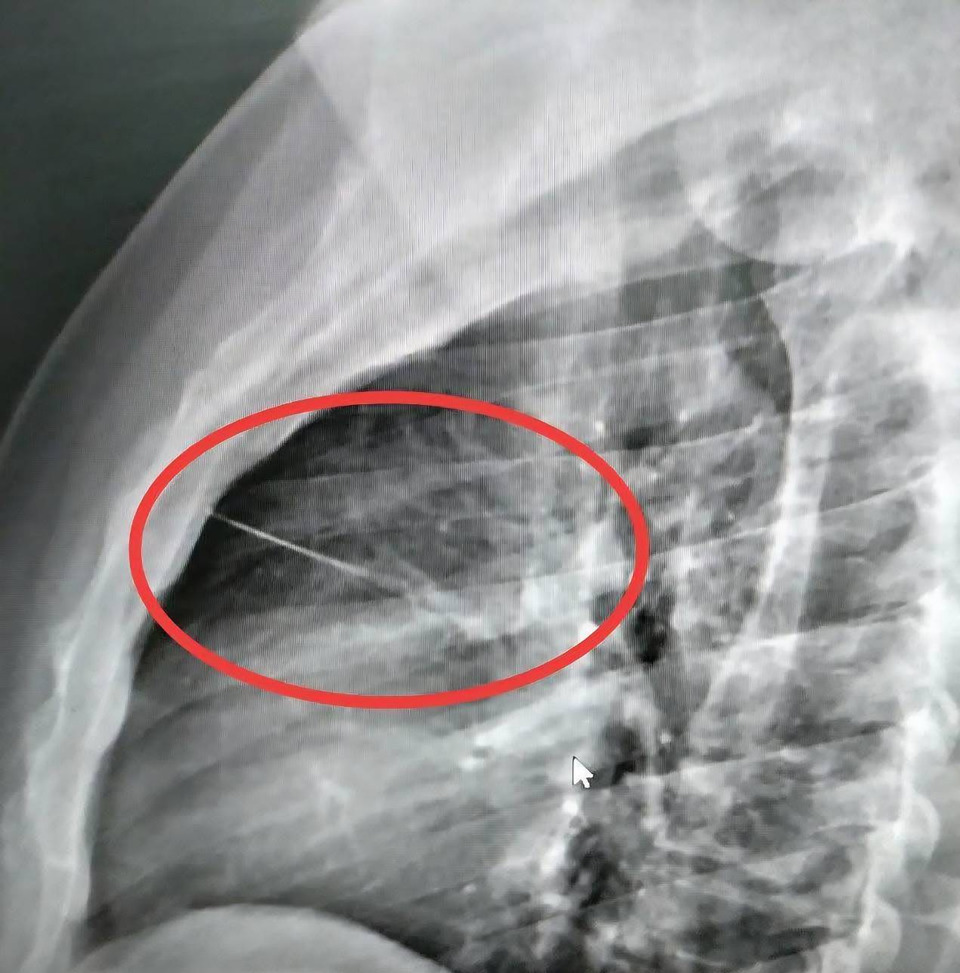

เมื่อไปถึงโรงพยาบาลอาการของนายบุญเลิศ ก็ยังไม่ดีขึ้นหมอจึงนำตัวไปเอ็กซ์เรย์ ปรากฏว่ามีวัตถุคล้ายของมีคมขนาดเล็กความยาวประมาณ 7 ซม.ทราบต่อมาว่าเป็นเข็มเย็บผ้า ฝังอยู่บริเวณหน้าอกซ้ายใกล้กับหัวใจ แพทย์จึงส่งตัวไปผ่าตัดที่โรงพยาบาลศูนย์บุรีรัมย์ เพราะเป็นจุดอันตราย